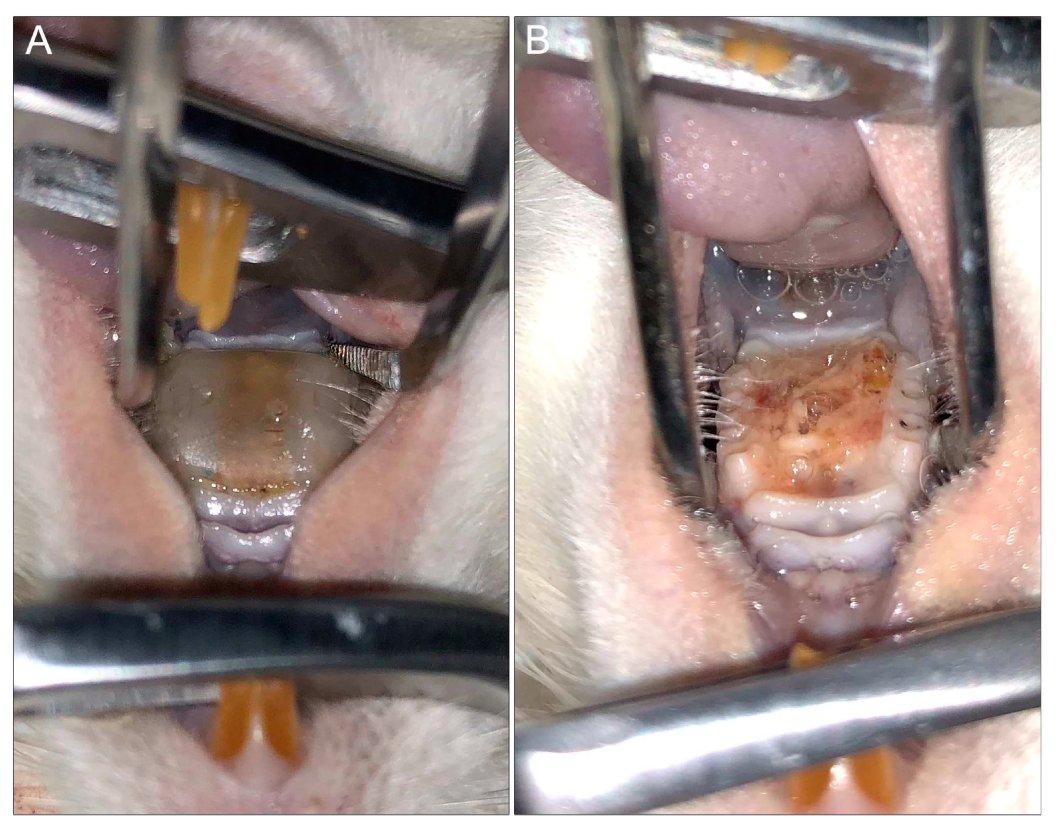

Figure 4.

Rat model of denture stomatitis. (A) Three-dimensional (3D)-printed denture with intimate fit to the hard palatal-mucosa of a rat. (B) Denture stomatitis in a rat model demonstrating profound edema and a thick yellow biofilm of the denture-bearing hard palatal mucosa (top: tongue; bottom: hard palate).